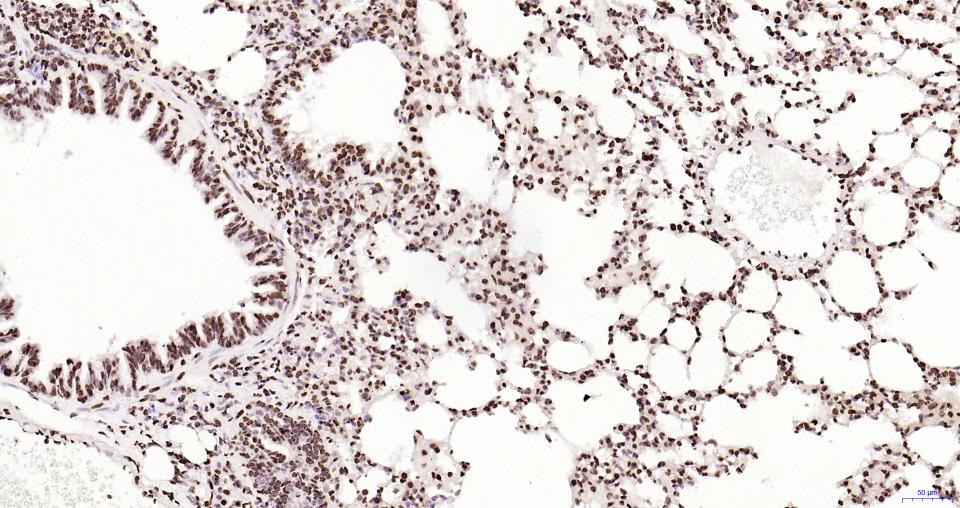

Paraformaldehyde-fixed, paraffin embedded Mouse Lung; Antigen retrieval by boiling in sodium citrate buffer (pH6.0) for 15 min; Antibody incubation with Histone H2A.X Monoclonal Antibody, Unconjugated(bsm-61080R) at 1:200 overnight at 4°C, followed by conjugation to the SP Kit(Rabbit, SP-0023) and DAB (C-0010) staining.

Paraformaldehyde-fixed, paraffin embedded Rat Lung; Antigen retrieval by boiling in sodium citrate buffer (pH6.0) for 15 min; Antibody incubation with Histone H2A.X Monoclonal Antibody, Unconjugated(bsm-61080R) at 1:200 overnight at 4°C, followed by conjugation to the SP Kit(Rabbit, SP-0023) and DAB (C-0010) staining.